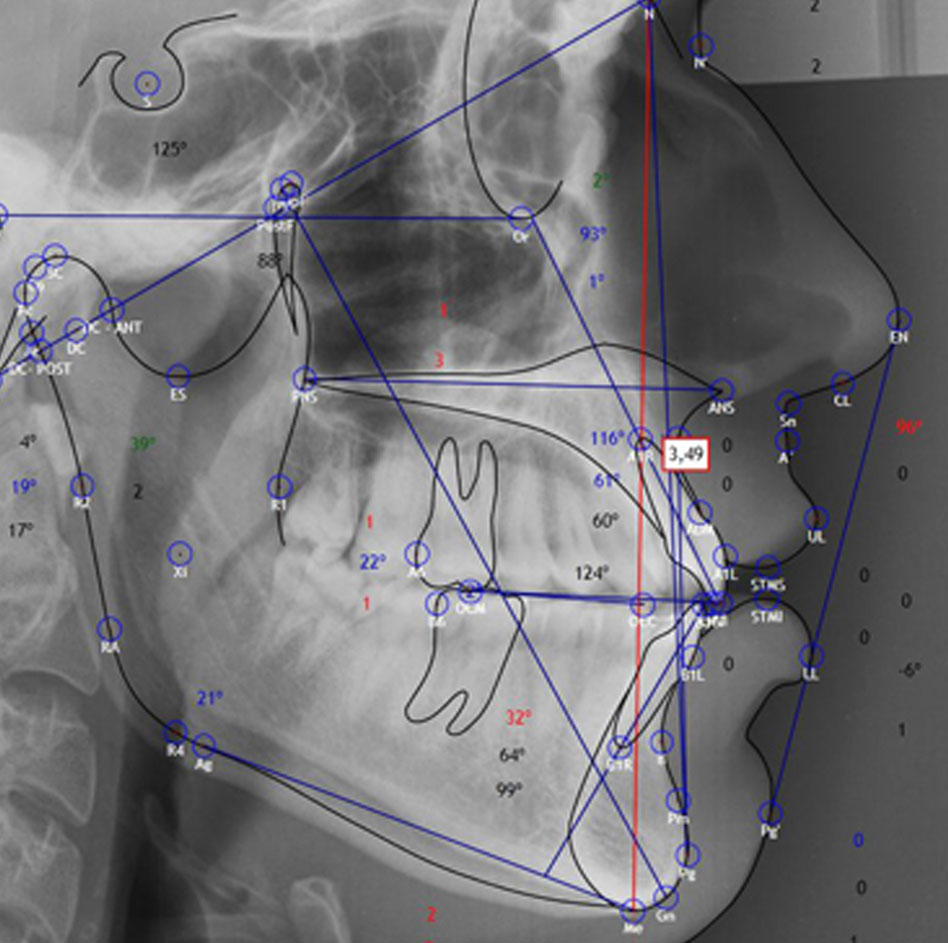

Ricketts, Ricketts frontal, Steiner, McNamara, Jarabak, tejidos blandos, y otros. Predicción de crecimiento, STO y VTO. Superposición de estudios cefalométricos, imágenes o ambos.